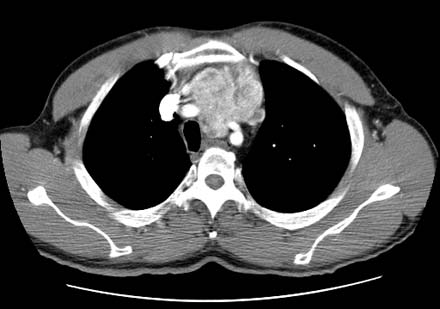

Glandula Tiroides Crecida - Bocio en el Cuello

Nota: Las imágenes se muestra para fines ilustrativos. No trate de sacar conclusiones comparando esta imagen con otras en el sitio. Solamente los radiólogos calificados deben interpretar las imágenes.